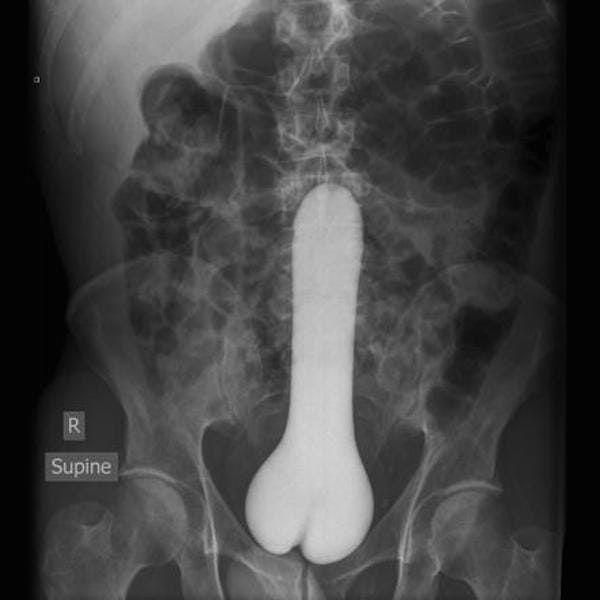

Dildo gets stuck up her ass - XVIDEOS.COMTo review this article, visit My Profile, then. This is exactly what you should do if you have a sex toy on your assBy the 24-year-old British woman Emma Phillips, recently made headlines for a unfortunate reason: One 7-inch that she had been using with her boyfriend disappeared into her ass. Phillips and her boyfriend looked around the bed for the sex toy once they realized it was missing, just to find out that he was still inside Phillips, buzzing. The couple tried—and failed—to remove the toy using a fork handle and barbecue clamps. Eventually, they called an ambulance, and the doctors surgically removed the toy. Phillips had to share live debacle updates, hoping to inspire others who had found themselves in a similar situation. You could be laughing, but Phillips isn't alone. Although his story might seem like a unique trip to the emergency room, Ph.D., sex therapist and relationships, tells SELF that it's nothing to be ashamed of. What happened to Phillips could happen to anyone who does not take appropriate precautionary measures. So if you're looking to give sex toy play an attempt, be careful. Here, the experts share their advice on how to bring — without ending in the ER. First things first: Get a toy with a flight base. 'Cause they're widening in the background, they're less likely to get trapped inside you. Toys with ropes or handles will also be enough, Michael Aaron, Ph.D., tells SELF, because they are easier to get out. If you're using anal beads or other toy that is, well, not a dildo, you'll want to make sure there's some recovery method (such as a handle, a rope or something else to keep the toy from disappearing completely inside you). And Fleming recommends playing with the toys on your own before taking them to play the mates. That way, you're more familiar with how they work. You will also know how deep you can insert them while you can comfortably remove them. Aaron says the next key to anal game is preparation - and . Suggest to start small: Use your fingers to prepare the area before trying to go bigger. This will help you relax the sphincter muscles in a low-risk way, after all, you can't lose your fingers! In terms of lubricant, you'll want to use enough to make things comfortable, but not so hard to control sex toys. And, you don't want to match the silicone-based lubricant with silicone toys because, it decomposes them and "relate things." Aaron says the water-based lubricant is usually a safe bet. One more thing: but you probably don't want it inside you. "A frozen banana or a hot dog could initially give pleasure," he says. "But as it warms up with the body temperature, also the risk of breaking." And let's be honest: The last thing you want is a piece of frozen hot dog trapped in your rectum. Just start: Breathe. "If you're scared and tense, you're also likely to hire your sphincter and muscles," Fleming says. "This will make it harder to find and remove [the toy]." Aaron recommends to use extra lubricant and keep relaxing; his partner could be able to grab the toy and pull it out. Fleming says you can put a leg on the toilet and get down as if you were defeating (or giving birth, if he ) to try to push the toy out, or at least get far enough to reach it with two clean fingers. When in doubt, call your gynecologist, or take a trip to the emergency room. , M.D., emergency doctor at Northwell Health, tells SELF that severe pain, discomfort, or bleeding after use are all signs that someone should seek immediate medical care. But it emphasizes that there is no need for panic: Sometimes things are lost where they should not. Fortunately, we have experts — like Huertas — to remove them when they do. And a trip to the ER is nothing to be ashamed of. "This could be embarrassing, but think of it as an honor in the exploration of pleasure," Fleming says. "Sex is sometimes messy and unpredictable, it's part of the journey. The more you play and explore, the more you discover how limitless the possibilities are." How's that for a chat? But seriously, experimenting with sex toys is totally fine. They can for some couples, and it's never good to embarrass someone for what they do in the bedroom. So, of course, you live. Just be careful to do so, no one wants to end up in the ER having a surgically removed sexual toy from its melting (even if it is worth a "bad sex honor"). Related:Also: Can you tell the difference between a sex toy and a beauty tool? (Glamour)SELF does not provide medical advice, diagnosis or treatment. Any information published on this website or by this brand is not intended as a substitute for the medical council, and should not take any action before consulting with a health professional. Sign up for our checkup In newsletterDiscover new training ideas, healthy recipes, makeup appearance, skin care tips, best beauty products and tips, trends and more from SELF.© 2021 Condé Nast. All rights reserved. The use of this site constitutes the acceptance of our (updated from 1/1/21) and (updated from 1/1/21) and the Fund can earn a portion of the sales of products that are purchased through our site as part of our Association of Affiliates with retailers. The material on this site cannot be reproduced, distributed, transmitted, recorded or otherwise used, except with the prior written permission of Condé Nast.